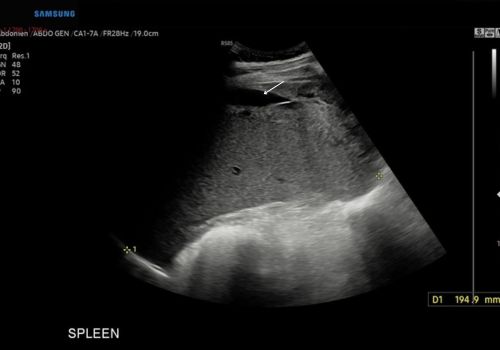

Figure 1

Figure 1 above Ultrasound confirms splenomegaly with a small volume of free fluid(arrow).